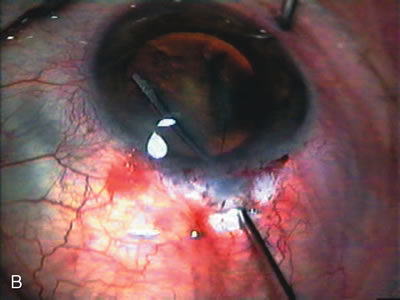

Fig. 4. Viscocanalostomy with deep sclerectomy and phacoemulsification. Nonpenetrating filtration procedures (NPFS) may be combined with phacoemulsification. Patients with mild disc damage and a history of limited topical drug therapy are the best candidates. Patients who require an IOP in the low teens are not good candidates for NPFS. By definition, NPFS is designed to lower IOP without penetrating into the anterior chamber, thereby avoiding the complications associated with trabeculectomy. Viscocanalostomy is intended to allow aqueous to percolate through a trabeculodescemetic membrane into a subscleral cavern created by the deep sclerectomy. The aqueous diffuses from the cavern into the dilated ostia of Schlemm's canal and into the episcleral venous plexus. A. Fashion a uniform 300-micron superficial scleral flap 1 mm into clear cornea. B. Construct a second 600-micron deep flap that facilitates the unroofing of Schlemm's canal, seen as the darker area. C. Use viscoelastic to dilate the ostia of Schlemm's canal. The major problem with viscocanalostomy is the eventual closure of the ostium decreasing flow to the episcleral plexus. D. Dissect the deep flap anteriorly into clear cornea creating the trabeculodescemetic membrane. This membrane is clearly seen between the scleral spur and the bend of the deep flap. The integrity of this membrane ensures the nonpenetrating portion of the surgery. Another problem with NPFS is the eventual fibrosis of this initially transparent membrane requiring goniopuncture. E. Deep sclerectomy gets its name from removal of the deep flap. Removal of this flap creates the potential subscleral space for accumulation of aqueous before it enters Schlemm's canal and exits the episcleral venous plexus. After removal of the deep flap, the superficial flap is sutured into place and conjunctiva closed. Approximately half of these procedures develop a shallow bleb.